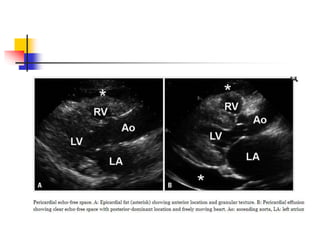

Pericardial Echo-Free Space: Epicardial

Fat vs. Pericardial Effusion

 Epicardial adipose tissue often appears as echo-free

space mimicking pericardial effusion in echo.

 Most adipose tissue distributes in atrio-ventricular or

interventricular groove.

 Excessive fatty infiltration tends to occur in old,

obese, and diabetic patients, particularly in women.

 differentiation of adipose tissue from fluid is based on

echogenicity, texture, mobility, and location.

 With exception of loculated effusion, free pericardial

fluid accumulates on dependent region, usually

posterior of left in supine position.

 Anteriorly located echo-free space is likely to be

epicardial fat deposition rather than pericardial

effusion .

 Mobility of adjacent tissue is a clue to

differentiation.

 As adipose tissue is less mobile than pericardial fluid,

surrounding epicardial and pericardial layer move

less freely in case of fatty infiltration.

 adipose tissue is more echogenic and lobulated than

fluid with homogenous echogenicity.

 CT imaging can definitely differentiate epicardial

adipose tissue from fluid collection in complicated

case.